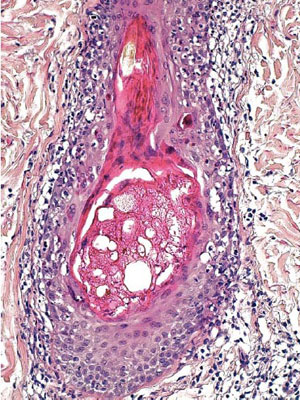

Le diagnostic s’établit sur des images, visualisées au microscope, de prélèvements cellulaires (biopsies, organes ou fragments d’organes, frottis, ponction de liquide).

Afin que les prélèvements soient visualisables au microscope, les techniciens du cabinet de pathologie vont réaliser sur ceux-ci des coupes ultra-fines, secondairement colorées puis mises sur lame de verre.

Le médecin va ensuite visualiser la lame et poser un diagnostic.